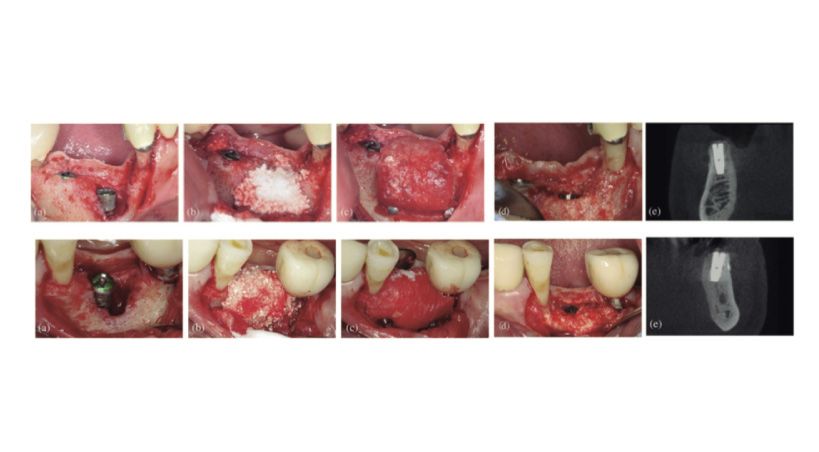

Análisis comparativo de dos biomateriales mezclados con injerto óseo autógeno para el aumento de crestas verticales

Un estudio histomorfométrico en humanos